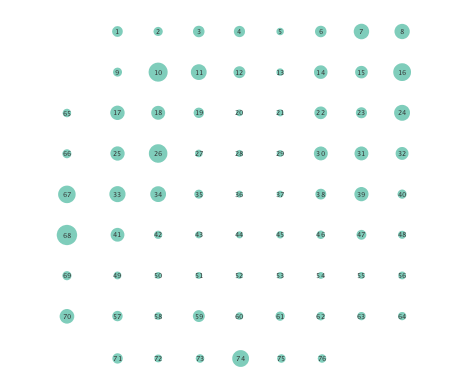

First, in- and out-degree was computed for nodes in each of the inferred networks. Note that the in-degree of a node counts its number of incoming edges, while the out-degree counts the number of out-going edges. The total degree per node sums the in- and out-degrees, and is indicative of how well-connected a given node is. Figure 3 depicts nodes in the network and their total degrees encoded by the radii of circles associated with the nodes. As expected from the previous subsection, Figures 3 (a) and (b) demonstrate that the linear SVARM yields both increases and deceases in the inferred node degree. On the other hand, the nonlinear SVARM leads to a more spatially consistent observation with most nodes exhibiting a smaller degree after the onset of a seizure (see Figures 3 (c) and (d)), which may imply that causal dependencies thin out between regions of the brain once a seizure starts.

In order to assess the information-routing abilities of brain regions before and after seizure onset, comparisons of the so-termed betweenness centrality were done. Betweenness centrality of a node computes the fraction of shortest paths between all node pairs that traverse the given node, and it is useful to identify the key information transmitting hubs in a network; see e.g., [24] for more details. The per-node betweenness centrality for each inferred network are depicted in Figure 4, with node radii similarly encoding the computed values. Little variation between preictal and ictal betweenness centralities is seen for the linear model (Figures 4 (a) and (b)), while variations are slightly more marked for the K-SVARM, see Figures 4 (c) and (d). It can be seen that modeling nonlinearities reveals subtle changes in information-routing capabilities of nodes between preictal and ictal phases.